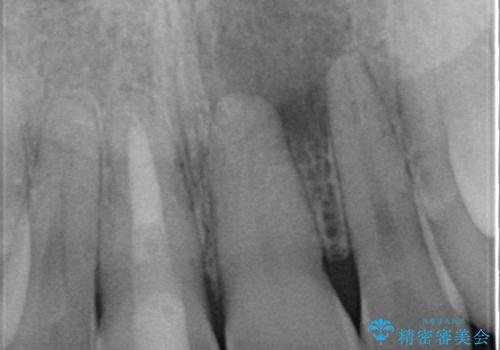

- 右上1番の色が暗いのを主訴に来院されました。

失活歯(神経の治療をしている歯)の場合、薬剤を歯の表面に塗布するホワイトニングでは白くなりません。歯の中に薬剤を入れて薬剤の反応を待つ必要があります。

治療手順としましては、マイクロスコープ(歯科用顕微鏡)を使用し、元々入っていた詰め物のCR(プラスチック)を除去します。その後、歯の中に薬剤を入れ、蓋をします。2週間後に来院して頂き、白くなっているかを確認します。ご本人がご満足頂く白さになるまで、これを3~4回繰り返します。今回は1回で患者様がご満足されたので治療を終了しています。

ウォーキングブリーチは外部吸収のリスクと色の後戻りのリスクがあります。